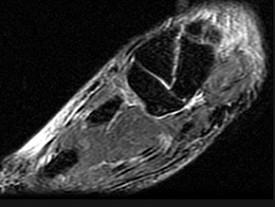

问题 女,25岁,扭伤后足中部痛,结合图像,最可能的诊断是 ( )

选项 A、中间楔状骨骨折 B、未见异常 C、外侧楔状骨骨折 D、足舟骨骨折 E、內侧楔状骨骨折

答案 E